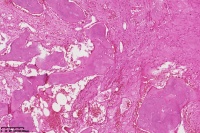

右胫骨内组织,单纯性骨囊肿?

性别

男

年龄

12岁

临床诊断

内生性软骨瘤?骨囊肿?

标本名称

右胫骨内组织

图3